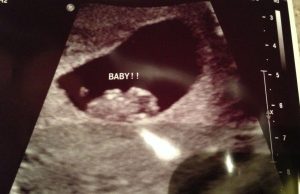

Bu metot ilk gebelik döneminde çekilen ultrason görüntüsünde plasentanın konumunu dikkate alır.

Uzuvlar gebeliğin dördüncü haftasından itibaren gelişmeye başlasa da Ramzi metodu sayesinde gebeliğin sekizinci haftasına kadar olan ultrason görüntüleri ile bebeğin cinsiyeti belirlenebilir.

Gebeliğin ilk dönemlerinde bebek plasentaya çok yakındadır. En önemlisi ise parlak alanı gözlemleyebilmektir.

İlk ultrasonunuzdan kalan görüntüleri bulun ve aşağıdaki adımları takip edin:

- İlk vajinal ultrason görüntünüzü bulduysanız, eğer fetüs sizin sol tarafınızda konumlanmışsa bu bebeğinizin cinsiyetinin kız olduğu anlamına gelir. Eğer fetüs sağ tarafınızdaysa bu bir erkek bebeğin işaretidir.

- Eğer ilk abdominal ultrason görüntünüzü bulduysanız sonuç bunun ayna görüntüsü olarak okunmalıdır. Bu demek oluyor ki plasenta sağ tarafta ise (ki bu gerçekte solda olduğu anlamına gelir) bu bir kız bebek beklediğinizi gösterir. Eğer plasenta sol tarafta ise (yani aslında sağ tarafta) bu bir erkek bebeğin habercisidir.

Eğer ultrasonu yorumlamak veya plasentayı bulmak sizin için zorsa endişelenmeyin, gidip doktorunuza danışabilirsiniz.